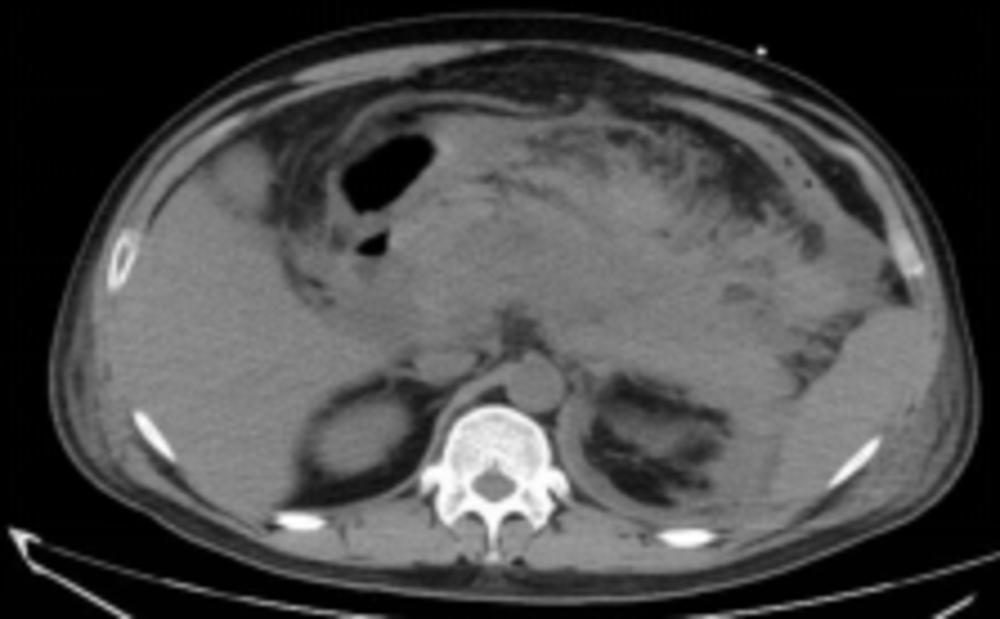

就诊时,小谢的腹部鼓得像球一样,经过血液、影像等检查,医生发现小谢的胰腺高度水肿、渗液,部分已坏死,结合验血结果,各种指标严重超标,其中甘油三酯和血淀粉酶非常高,诊断为重症胰腺炎。

患者腹部CT提示胰腺高度水肿、渗出,部分坏死